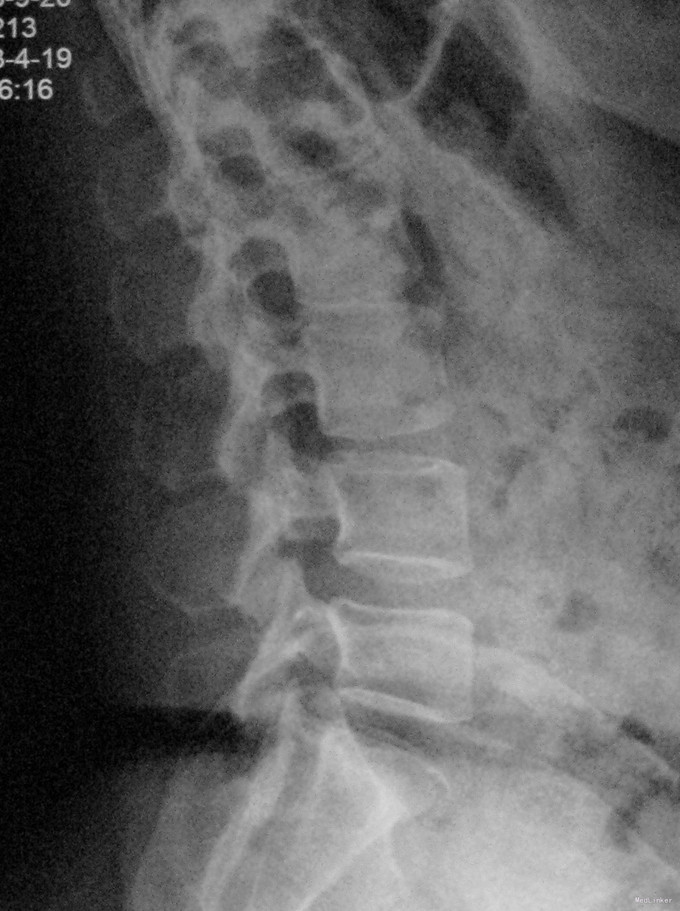

查体:脊柱生理弯曲存在,腰椎活动受限,L4/L5棘突压痛叩痛,叩击痛。双侧直腿抬高试验(-)。双下肢皮肤感觉正常,双侧髂腰肌、股四头肌、双侧胫前肌、踇背伸肌肌力Ⅳ级,腹壁反射、肛门反射正常,两侧膝正常,双侧踝反射未引出。双侧Babinski征(-),双侧皮温及色泽正常,双侧足背动脉搏动良好。 辅助检查:X光片示:动力位片显示腰椎4/5椎间失稳。MRI检查显示:腰4/5椎间盘突出,黄韧带肥厚致椎管狭窄,相应节段硬膜囊受压改变。

诊断:腰4/5椎管狭窄并失稳症。 治疗:给予行后路腰4/5右侧椎板间开窗减压椎间盘摘除并肥厚黄韧带切除+棘突间wallis固定术。